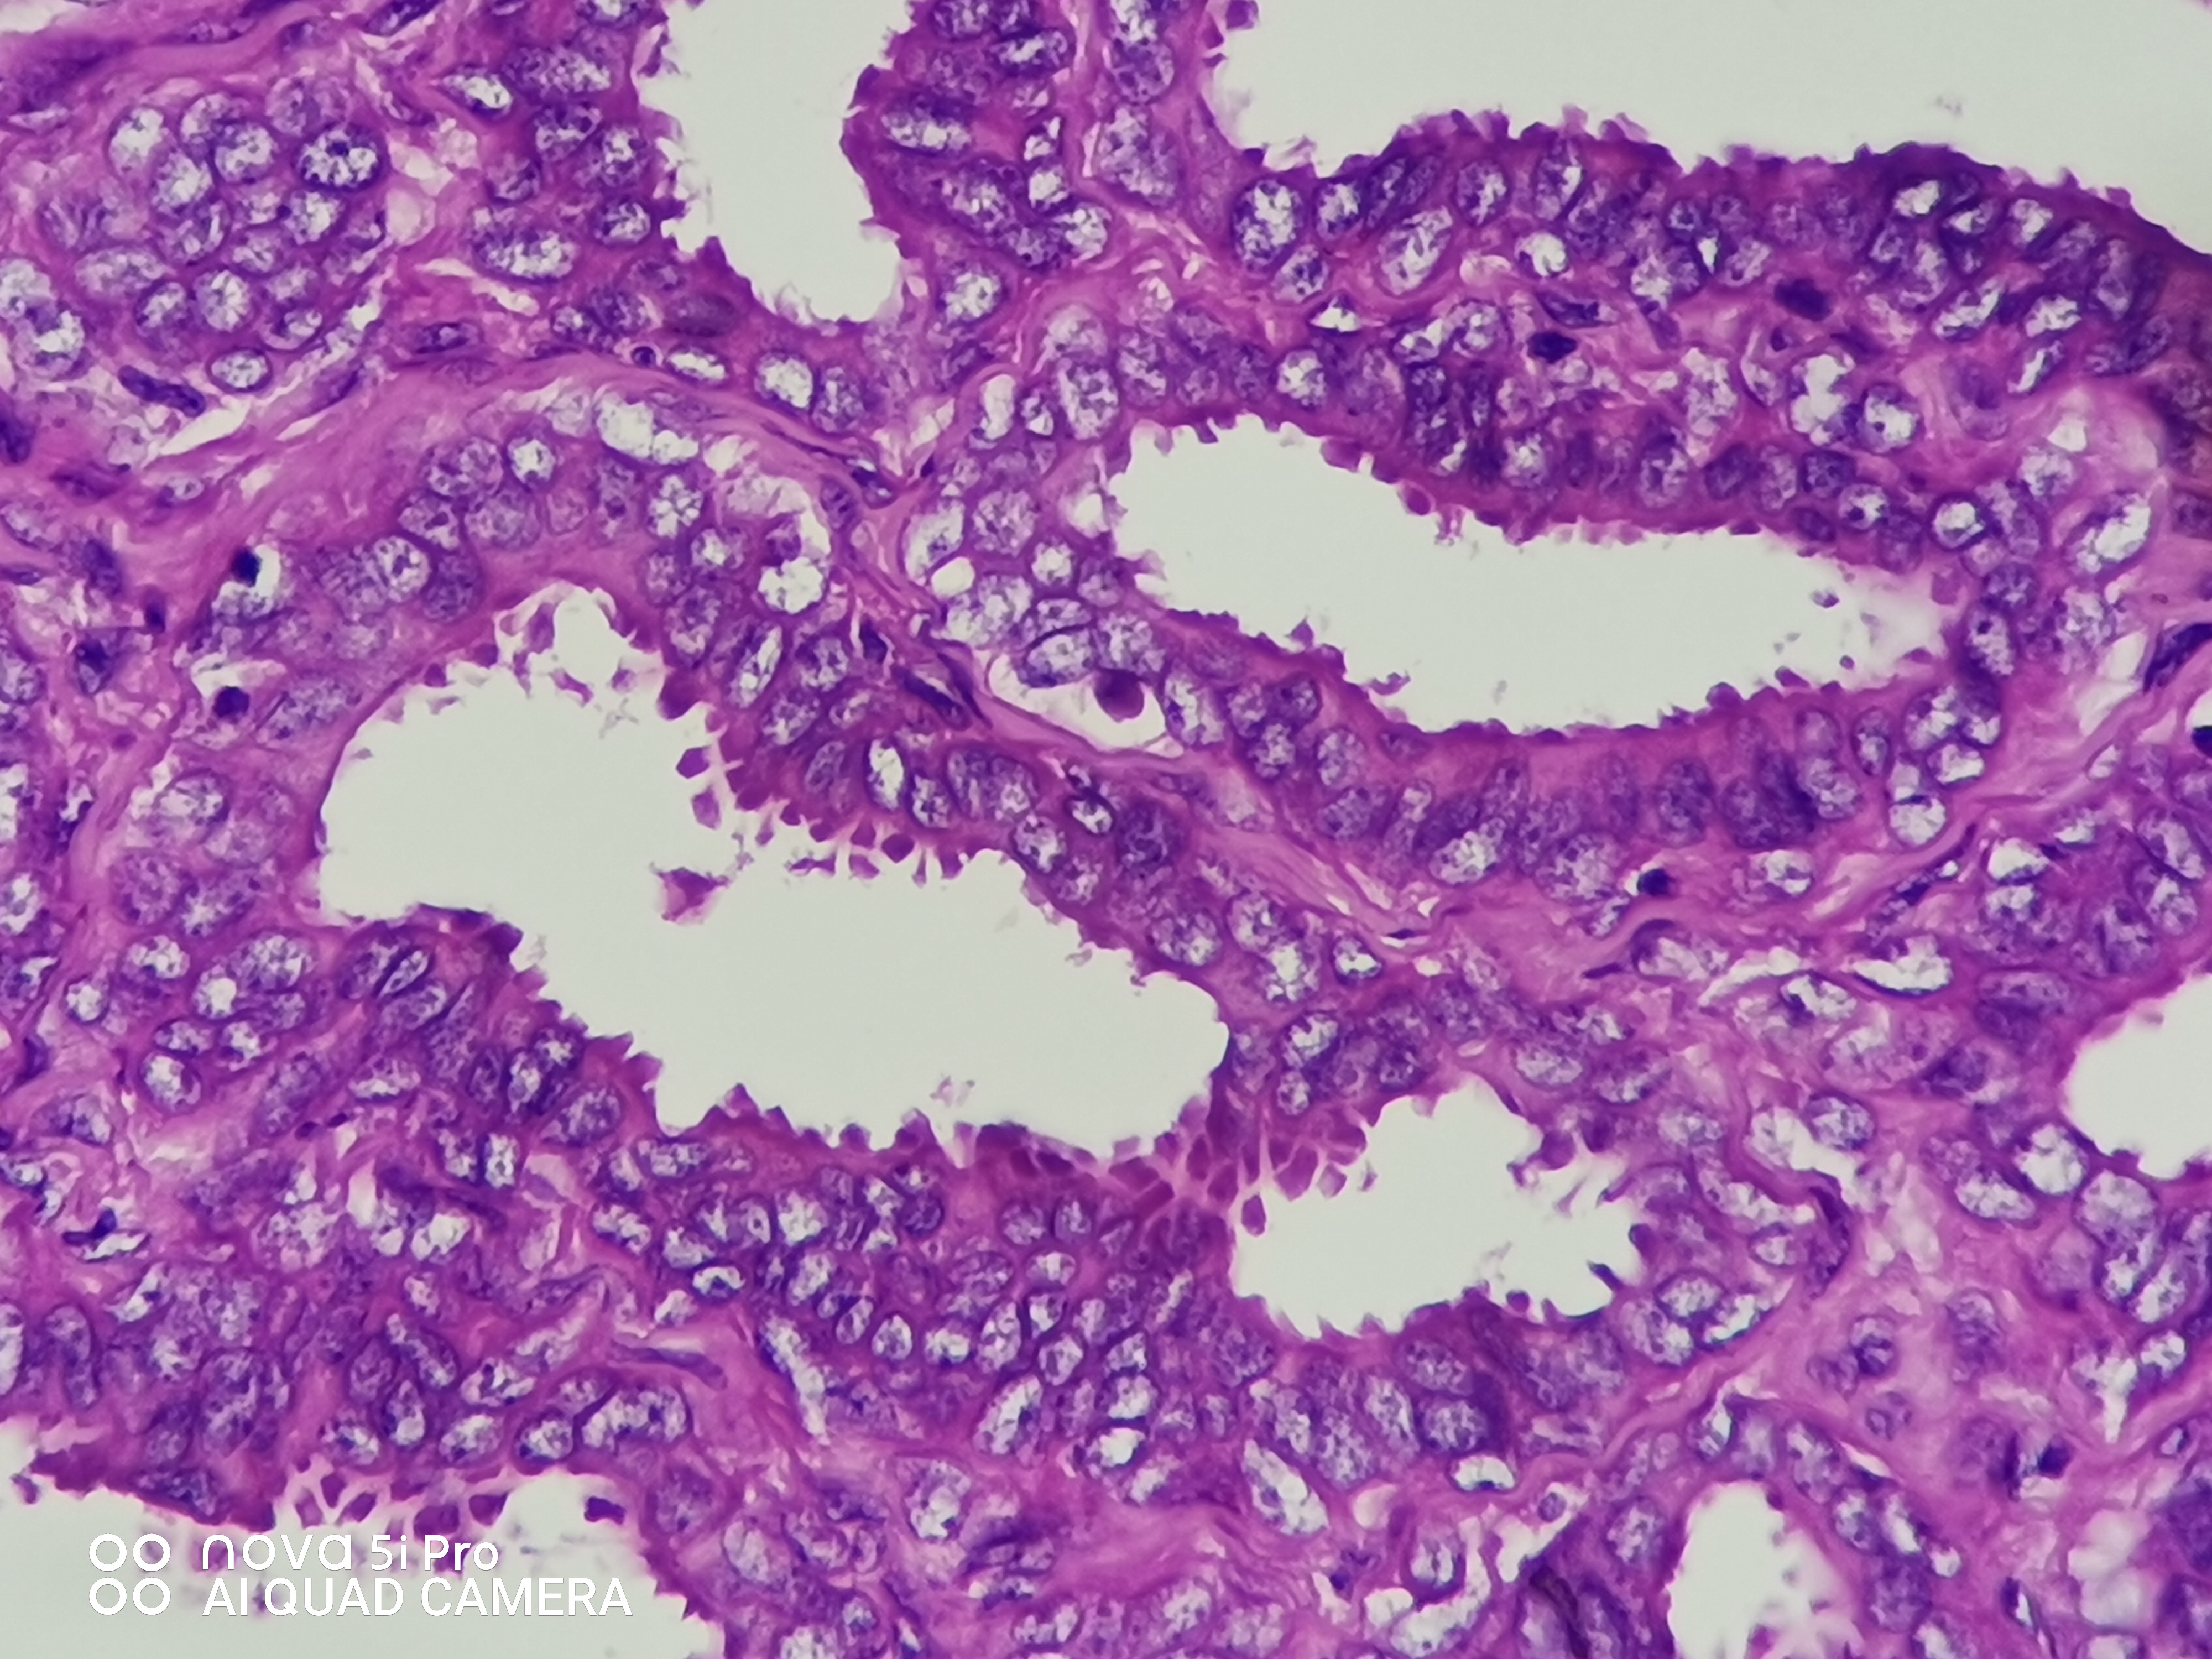

性别年龄41岁临床诊断混合痔,肛门肿块性质待查。

一般病史肛门肿块反复脱出5年,加重2月余。

标本名称肛门肿块

大体所见组织一块,大小约0.7*0.5*0.5cm,对半切开,实性灰白质中,全取。

高级别乳头状肿瘤

考虑:癌变!

乳头状汗腺瘤?

• 云子:  如果是肠上皮的话会有纤毛细胞,会有杯状细胞。杯状细胞的消失对应的是高级别肠上皮细胞病变,然而切片不支持高级别。女性外阴、肛门的这种乳头状生长模式十断头分泌现象,我更首先考虑乳头状汗腺瘤。个人意见,仅供参考!

图1可见断头式分泌,需要鉴别 汗腺肿瘤,标一下CK7.CK20.SATB-2.和P63。

这个病例的医生刚刚打电话联系我了,经省里专家远程会诊也是考虑乳头状汗腺瘤伴轻一中度非典。